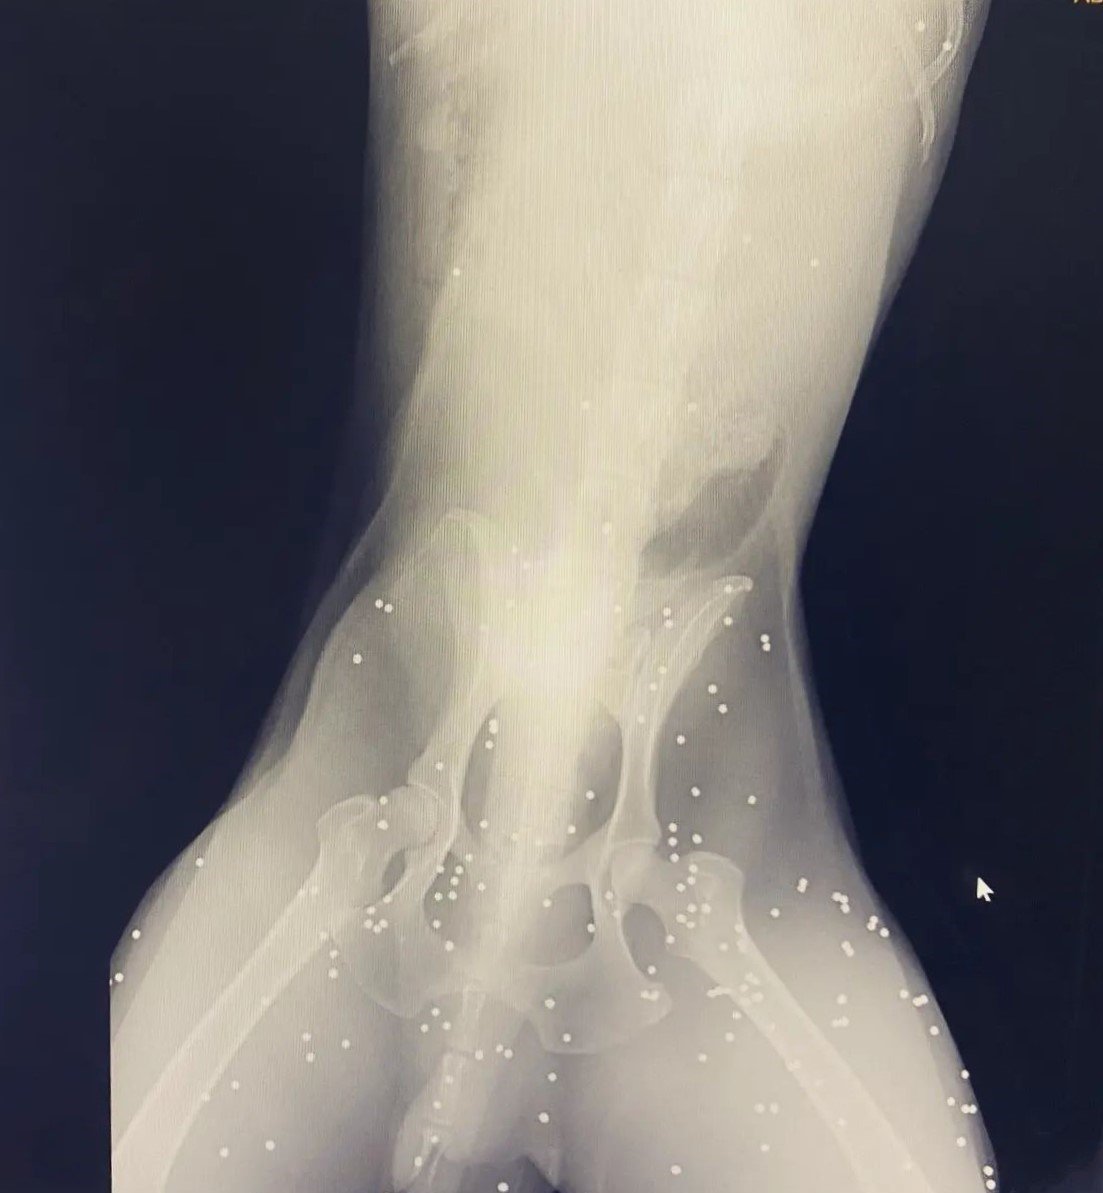

Av tüfeği ile vurulan köpeğin vücudunda 100’den fazla saçma tespit edildi

Kastamonu'nun Abana ilçesinde av tüfeği ile vurulmuş halde bulunarak tedavi altına alınan köpeğin vücudunda 100'den fazla saçma tespit edildi.

Olay, Kastamonu'nun Abana ilçesinde meydana geldi. Edinilen bilgiye göre, yaralı halde bulunan sokak köpeğini gören hayvanseverler, durumu Abana İlçe Emniyet Amirliğine bildirdi. Yaralı köpek bulunduğu yerden alınarak veteriner kliniğinde getirildi. Veteriner hekim tarafından çekilen röntgen filminde köpeğin vücudunda 100'den fazla saçma olduğu görüldü. Tedavi altına alınan köpeğin 48 saat müşahede altında tutularak, sağlığına kavuşmasının ardından salınacağı öğrenildi.